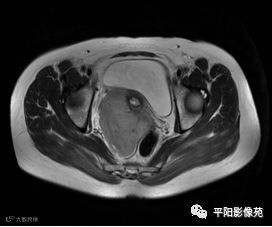

MRI表现

T2轴位

(宫腔内见金属节育环伪影)宫颈区见不规则形等T1稍长T2信号软组织肿块,DWI序列呈明显高信号,大小约为3.87cmX2.64cm,双侧宫颈基质低信号环连续性中断,病灶向子宫右后上方生长,周围脂肪间隙模糊,增强扫描明显强化,强化程度低于子宫及宫颈实质;子宫后方、子宫直肠间隙见不规则形长T1长T2信号软组织肿块,DWI序列呈高信号,大小约10.12cmX4.82cmX10.29cm,病灶呈分叶状,向下方生长与宫颈分界不清,与直肠分界尚清,增强扫描明显不均匀强化。